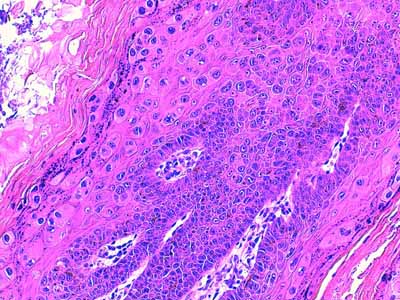

A l’examen histologique, on observe des néoformations verruqueuses, exophytiques, constituées d’un épiderme bien différencié, sévèrement hyperplasique, produisant à la surface du tégument, des projections digitées, longues et étroites (Fig 2). Cet épiderme est le siège d’une sévère hyperkératose orthokératosique ou parakératosique et d’une hypergranulose avec de volumineux grains de kératohyaline (Fig 3 &6). Sa couche basale est très développée, cellulaire, mitotique, hyperbasophile (Fig 4 & 5). Les acanthocytes sous-cornés sont vacuolisés (Fig 3 & 7). Ils montrent un cytoplasme bleuté, discrètement fibrillaire (Fig 6), ou vacuolisé, leur noyau parfois pycnotique étant entouré d’un halo clair. Il s’agit de koïlocytes (Fig 7). Certains montrent un noyau avec margination chromatinienne laissant un centre bleuté compatible avec une inclusion basophile (Fig 7). Dans le derme papillaire sous-jacent, on observe un infiltrat inflammatoire lympho-plasmocytaire d’intensité modérée. Absence d’image suspecte de malignité.

Photo 4 (Hémalun-Eosine X200) : L’épiderme hyperplasique émet

des papilles coniques, au plancher desquelles la couche basale

est très développée et hyperbasophile. Le derme papillaire

est le siège d’un infiltrat lympho-plasmocytaire modéré.